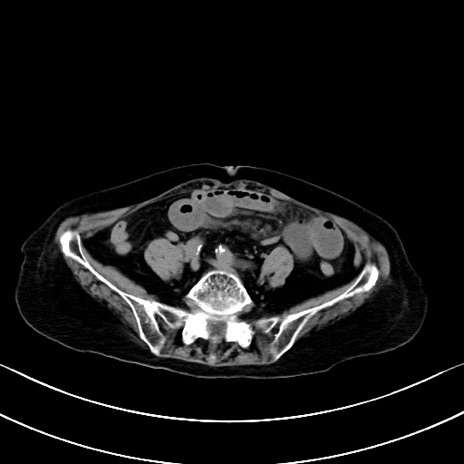

横断像

他院CT